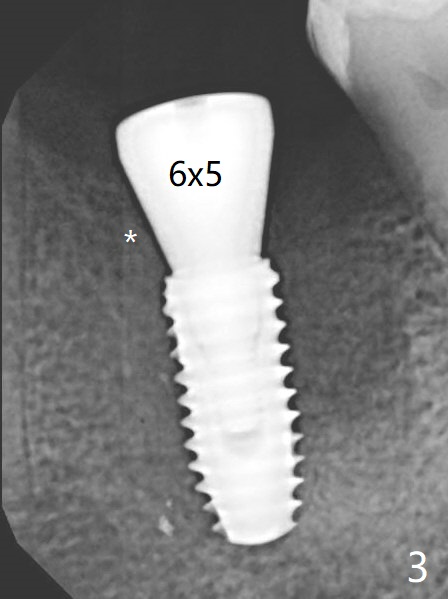

A 4.5x10 mm implant is well placed at #19 in term of trajectory with guide (Fig.1). Because of crestal bone resorption, the implant is placed deep with increased potential of abutment screw loosening. The key to prevention of bone loss is socket shield. A 6x5 mm healing abutment is placed with 10 Ncm (Fig.3 (PA taken 21 days postop)).